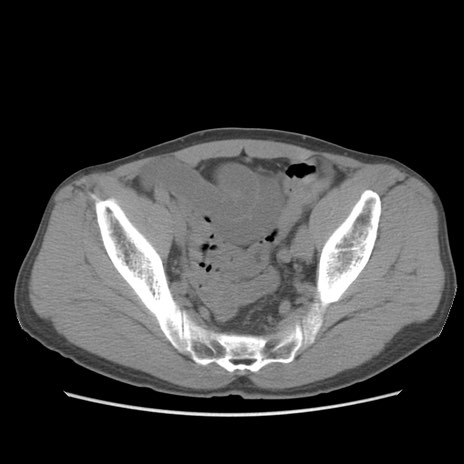

症例56 CT(横断像)

脂肪ウインドウ